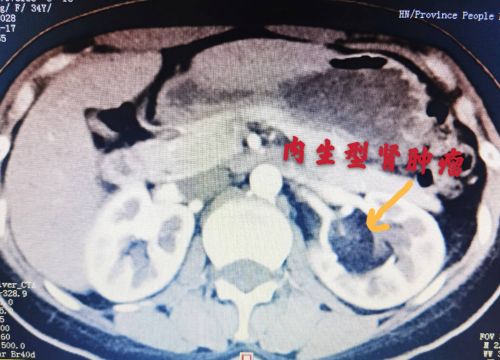

增强ct显示:左肾内有一个内生型肿瘤。

郭玺副主任医师详细询问病史,并查阅各项检查结果发现,肿瘤起始于陈女士左侧肾门(肾动脉、肾静脉等血管出入的地方),向内侵袭至肾脏中央,不仅位置刁钻、形状奇特,还与肾实质紧密相连、融为一体,属于典型的内生型肾肿瘤。